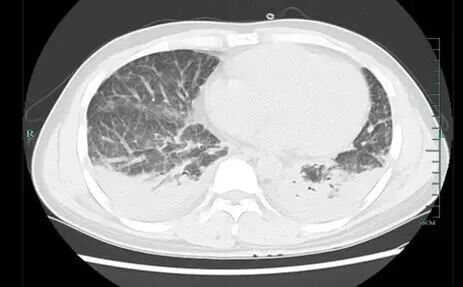

壮哥经检查:胸部CT双肺弥漫性病灶,血氧饱和度指标不到70%。“重症肺炎,I型呼吸衰竭。再拖下去有生命危险!”他随即被安排住院治疗,并做了基因检测,揪出了真凶——马尔尼菲篮状菌。

壮哥的肺部情况